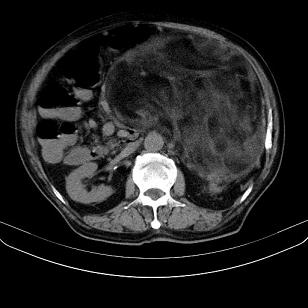

标题: CT21671:男,88岁,左上腹包块 [打印本页]

标题: CT21671:男,88岁,左上腹包块

患者因咳嗽而住院,自觉右上腹包块,无其他不适。

腹膜后高分化脂肪肉瘤

腹膜后脂肪肉瘤

腹膜生占位性病变,脂肪肉瘤可能。

左侧腹膜后脂肪肉瘤。